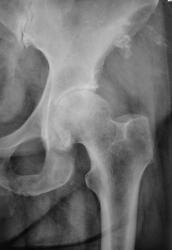

Крупный мягкотканный + компонент с атрофией, - объемом и склерозом контура прилежащей подвздошной кости, с бесформенными очаговым оссификатами параоссальной зоны. В ТБС помимо картины артроза (сужение щели, склероз, остеофитоз) имеются также полости просветления головки, сочетанные с перфокальным остеосклерозом. Фиброматоз?

Кроме деформирующего коксартроза II ст. здесь есть самостоятельная патология головки бедра: один крупный и 2 – 4 мелких очага деструкции(?). Это могут быть, например, литические метастазы, энхондромы…. Кто больше?

Головка в средней трети - с костными эрозиями . Ревматоидный артрит 2 Rстадии?

ДОА 3ст, пятнистый остеопороз, создающий впечатление наличия кистозных просветлений в головке БК. Остеохондропатия(?) ветви седалищной кости.